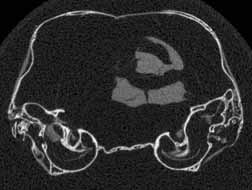

Several features of mammalian development are visible in members of the growth series shown on this website. An obvious change is the thickening of the skull elements as ontogeny progresses -- particularly the bones that surround the braincase and the ear region (contrast the thickness of the bones in the unreduced coronal slice #401 in day 27 and the unreduced coronal slice #390 in day 90, shown below). A feature associated with the thickening of the skull bones is the closure of the parietal fontenelle between days 48 and 57.

Reduced coronal slice #401 through the braincase of day 27 specimen. Click on the thumbnail for an unreduced version. |